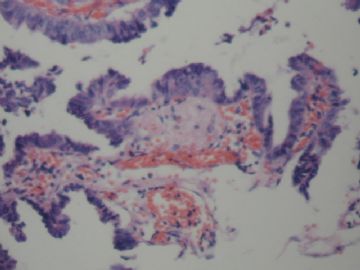

• 胆囊图3

图3

慢性胆囊炎 腺体中度不典型增生

腺癌,像是粘液腺癌,不知在显微镜下粘液是否明显.

腺体重度异型增生(注意有无明确浸润)

无明显浸润,诊断癌证据不足。

考虑慢性胆囊炎,局部腺体中重度不典型增生

诊断癌证据不足。慢性胆囊炎 腺体中度不典型增生

局部见腺体中度不典型增生。标记P53和增殖活性(Ki-67) 。

不够癌,不典型增生-中度